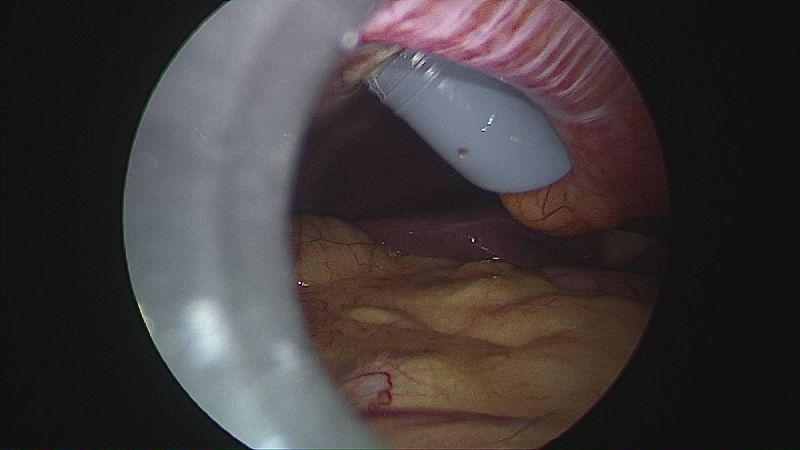

Gastrectomia longitudinală (gastric sleeve) este o intervenție care produce scăderea în greutate prin două mecanisme: restrictiv (îndepărtează o mare parte din stomac lăsând un rezervor de 80-120 ml) și hormonal (prin extirparea fundului gastric se reduce semnificativ secreția hormonului foamei, grelina).

Operația ”de micșorare a stomacului” se realizează miniminvaziv (laparoscopic) și constă în îndepărtarea marii curburi gastrice cu păstrarea antrului gastric și a micii curburi sub forma unui tub calibrat pe o sondă.

Tehnica aduce beneficiile chirurgiei laparoscopice, durere redusă, externare în primele 48 ore de la intervenție. Avantajul său constă în confortul oferit pacientului care prezintă senzația de sațietate rapid prin umplerea unui stomac de doar 100 ml, reducerea senzației de foame prin suprimarea secreției de grelina. De asemenea, nu modifică traseul alimentelor, nu exclude segmente digestive din circuit și pierderea excesului ponderal poate ajunge până la 100%.